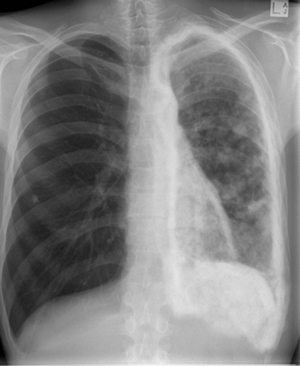

Lung encasement by metastatic osteoblastic sarcoma

Med J Aust 2007; 186 (2): 100. || doi: 10.5694/j.1326-5377.2007.tb00819.x